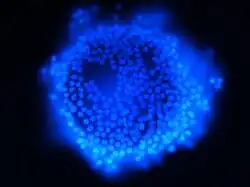

Cellule de la granulosa

Durant la première partie du cycle, les cellules de la granulosa se multiplient pour former plusieurs dizaines de couches autour de l'ovocyte (stratification de la granulosa). Par la production de glycoaminoglycanes se créent dans leur épaisseur des cavités remplies de liquide folliculaire. Par confluence, elles donnent une cavité unique centrale, l'antrum, tandis que l'ovocyte entouré d'une seule couche cellulaire (future corona radiata) est rejeté en périphérie.